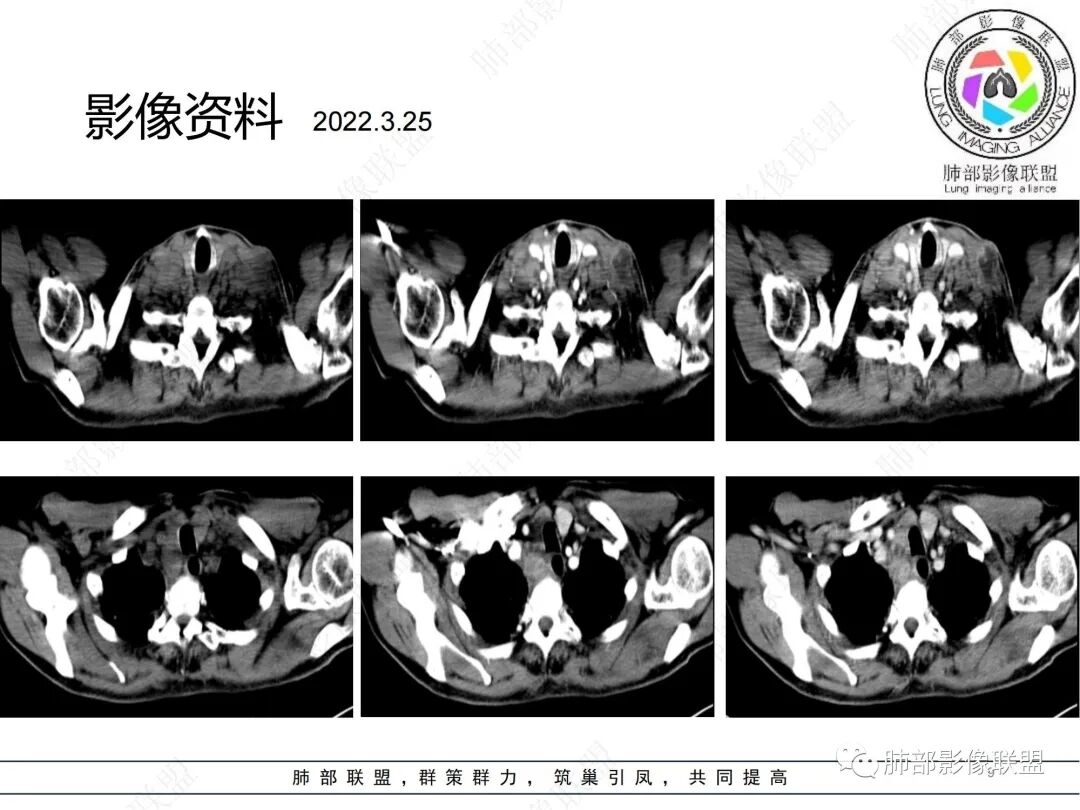

2、影像特点:双肺多发结节及条索影,边缘清晰,右肺上叶可见网格影,右侧胸腔少量积液;颈部、纵膈及腹部多发淋巴结肿大,大部淋巴结强化不均,呈环形强化,内部见低密度坏死区,部分淋巴结坏死不明显,尤其是腹部淋巴结密度较均匀。